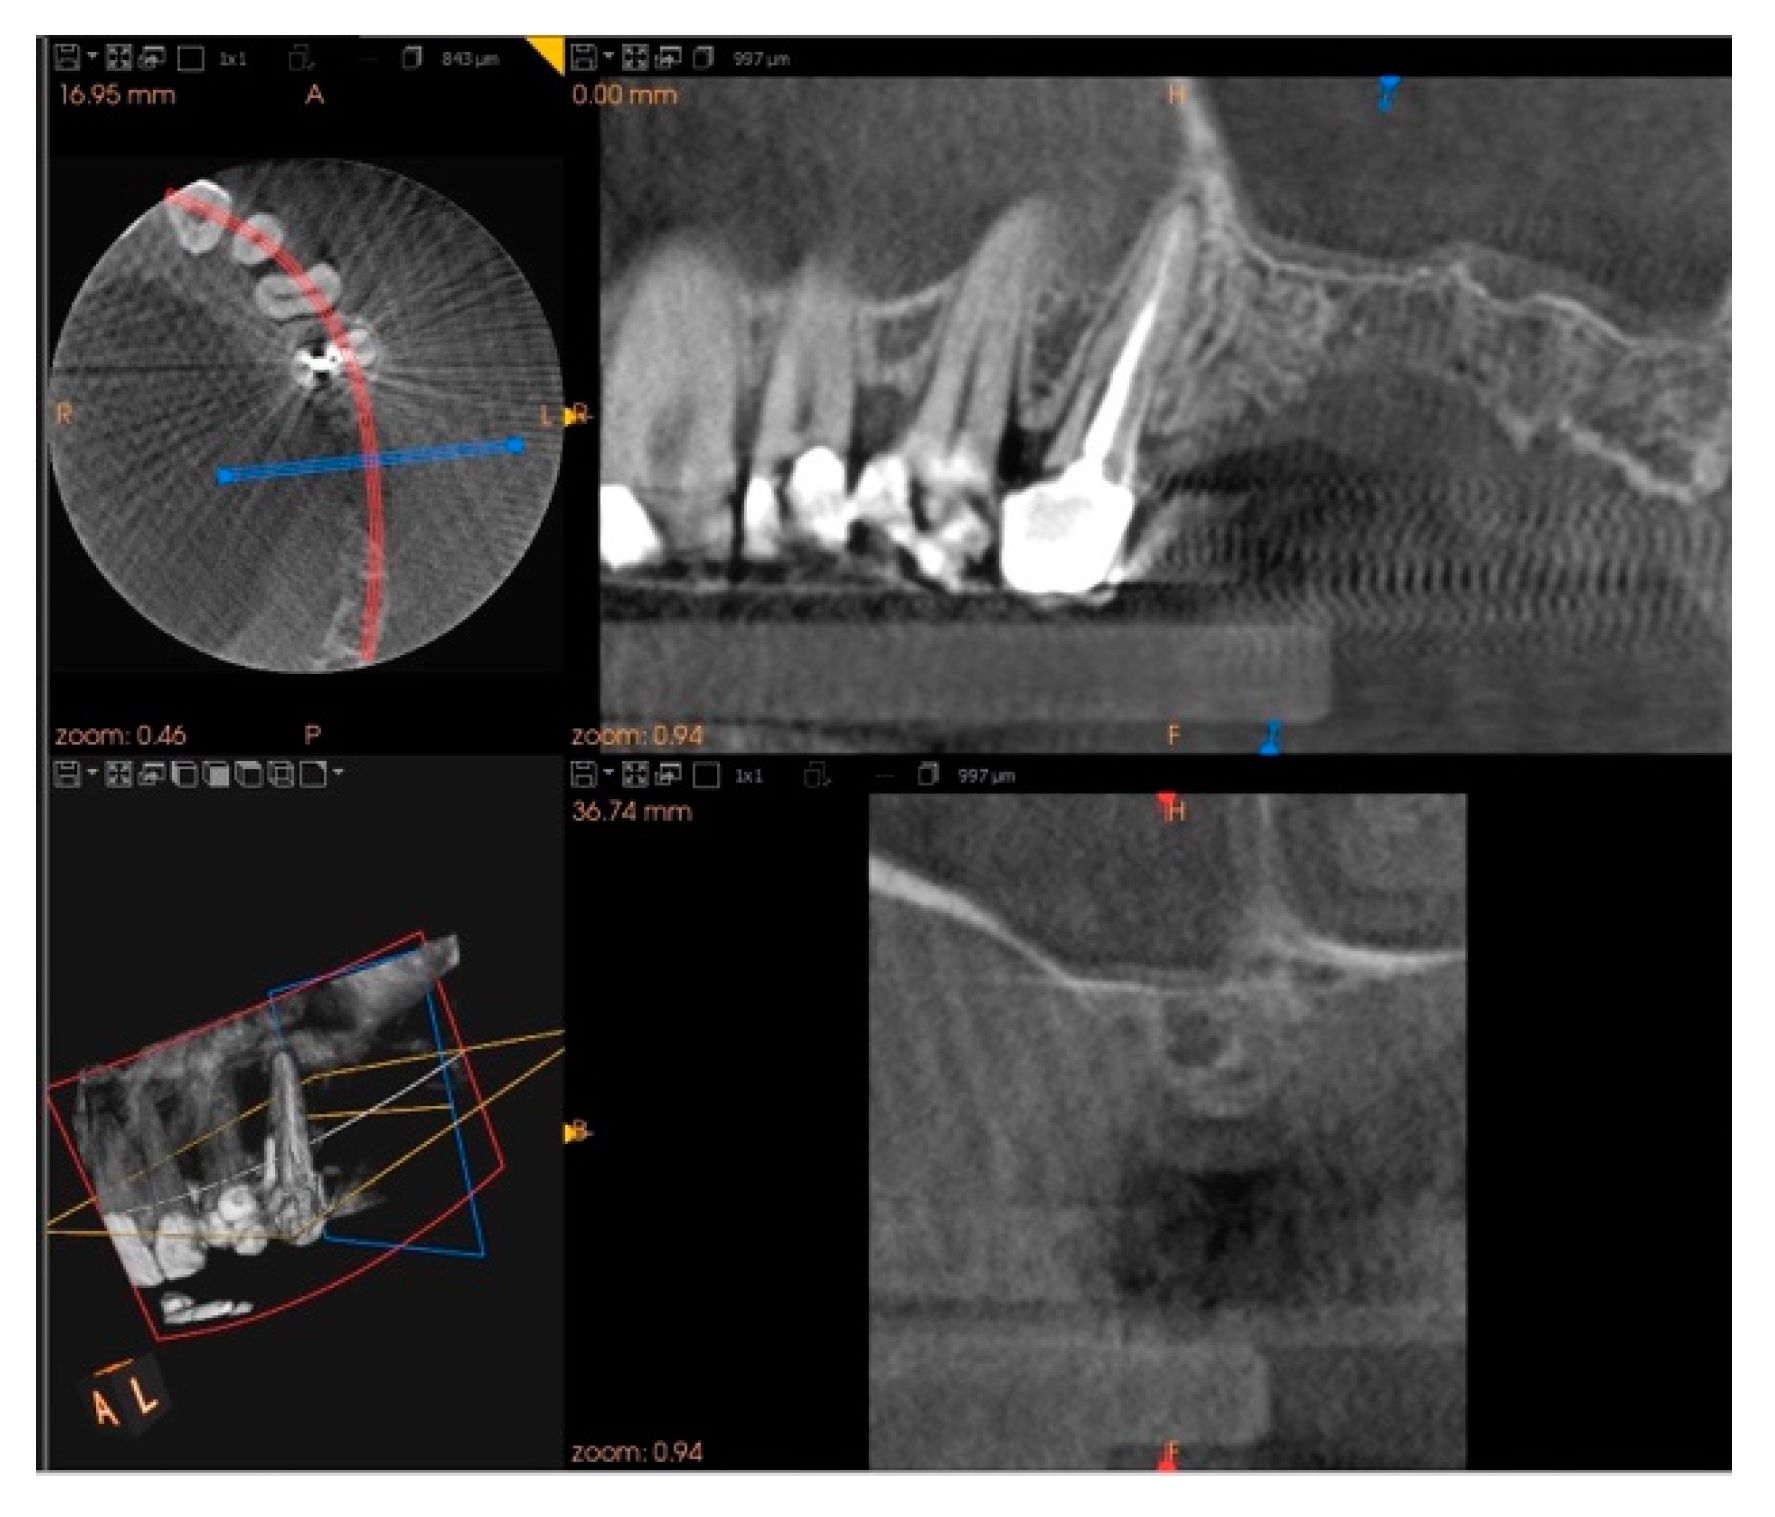

2. Case Report